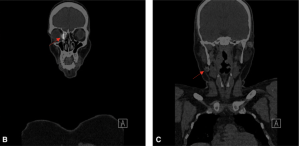

Studies have also examined the utilization of single photon emission computed tomography/computed tomography to help more precisely localize the SLN.[9][14][18][23][24]Initially, studies utilized a dual-dye technique in which a small amount of isosulfan blue dye (0.2 cm3) to aid in visualization was injected; however, this has become a less commonly utilized practice given the concern of staining the conjunctival surface.[8][15]The use of indocyanine green-guided sentinel lymph node biopsy as an alternative to technetium-99m has been examined in a small number of studies; however, Tc-99m remains standard practice.[25]